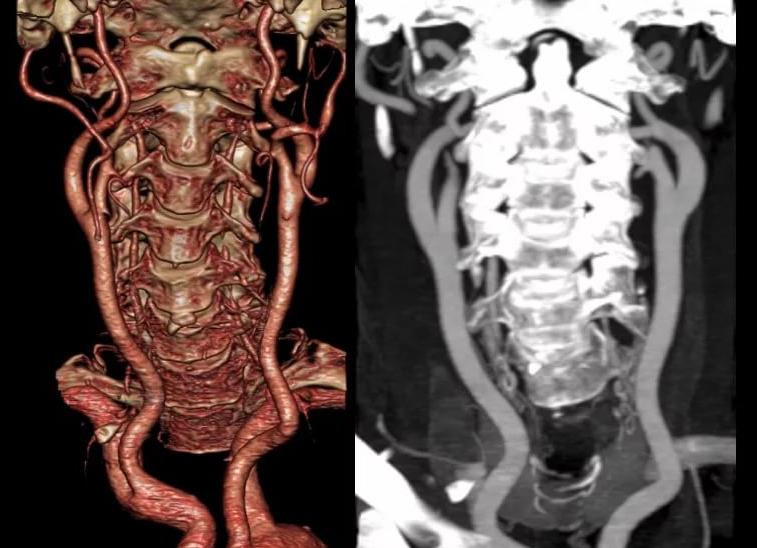

КТ позвоночника использует для создания изображений костей рентгеновские лучи. Источник излучения (трубка) вращается вокруг тела пациента, напротив нее находится детектор (приемник) сигналов. За секунду посылается около 1000 рентгеновских сигналов, оборот трубки вокруг тела занимает 1-2 секунды. Всего производится около 30 оборотов. Такая высокая частота позволяет получить качественные изображения костных структур, хорошо задерживающих рентгеновские лучи.

Этот метод основан на измерении ослабления рентгеновского излучения, проходящего через тело человека в различных проекциях. КТ-томограф позволяет получать послойные тонкосрезовые изображения, устраняя их наложение друг на друга. Его чувствительность к мелким изменениям как минимум в 10 раз выше, чем у рентгеновского аппарата. Компьютерная томография быстрая и безболезненная, однако проходить ее часто все же не рекомендуется, поскольку рентгеновское излучение может негативно воздействовать на организм пациента.

Это современный метод обследования патологий позвоночника с получением послойного изображения тканей или органов. Дает намного лучшие и более подробные результаты, чем при проведении обычной рентгенографии. При таком исследовании используется то же рентгеновское излучение.

В основе КТ лежит свойство рентгеновского излучения по-разному поглощаться в зависимости от того, какую плотность имеет исследуемая ткань. По сути, это та же рентгенография, однако при этом изображение получается с помощью компьютерной обработки сигналов.